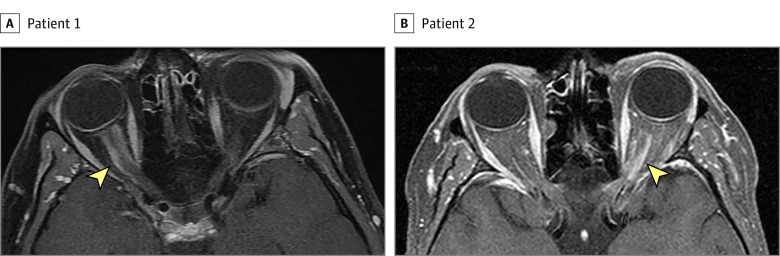

It is noteworthy that 11 of the 16 patients with a misdiagnosis (68.8%) who eventually received a diagnosis at our institution had their MRI results misinterpreted. Five of these MRIs were misread by radiologists who were not trained in neuroradiology and 6 were misread because the test was ordered incorrectly (not including orbital images and contrast administration). Radiologists have a key role in disease detection (Figure 2).22,23 For many neuro-ophthalmological diseases, neuroimaging is mandatory to accurately diagnose and manage the problem. Most radiological centers are equipped with advanced MRI devices; however, a lack of neuroradiology training among the interpreting radiologists may lead to devastating diagnostic errors.24,25 Inappropriate imaging protocol selection is another factor that leads to misdiagnosis. Our impression is that most clinicians fail to order orbital images and contrast-enhanced sequences for patients who present with progressive visual loss. Additionally, several insurance companies in the United States systematically deny dedicated orbital imaging when ordered in addition to a brain MRI, which contributes to inappropriate imaging techniques.

Figure 2. Optic Nerve Sheath Meningioma on Orbital Magnetic Resonance Imaging (MRI).

Axial T1-weighted contrast-enhanced orbital MRI with fat suppression shows an obvious right (A) and left (B) optic nerve sheath enhancement (arrowhead) that led to the correct diagnosis of optic nerve sheath meningioma. The optic nerve itself does not enhance. Both patients previously had a brain MRI without dedicated orbital views on which the optic nerve sheath meningioma was missed.